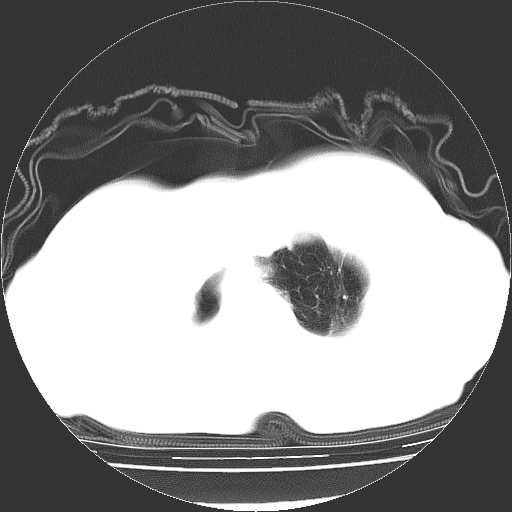

标题: CT23991:女,72岁,咳嗽、憋气一周。 [打印本页]

女,72岁,咳嗽、憋气一周,十年前曾患肺结核及胸膜结核。

右侧毁损肺,右侧纵隔疝

右侧毁损肺,右侧纵隔疝,左肺代偿!

1.右侧损毁肺伴胸膜钙化,2.左肺小结节灶,良性可能大,注意复查。3.肝脏左叶囊肿。4.先天性一侧肺不发育待出外(右侧胸廓无明显塌陷)。对比原片应该非常有帮助。